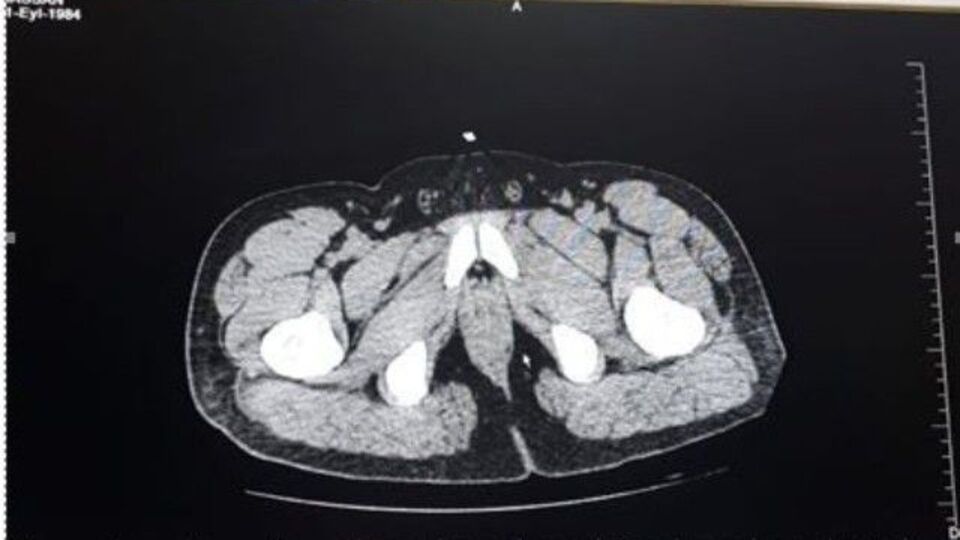

Tayland basınındaki haberlere göre, gümrük memurları x-ray cihazından geçen Suamu Nkele'nin midesinde bazı maddeler göründüğünü tespit etti.

İncelemeler sonrası midesinde 1,2 kilogram uyuşturucu madde bulunan kadının çorap ve iç çamaşırlarına da uyuşturucu yerleştirdiği ortaya çıktı.